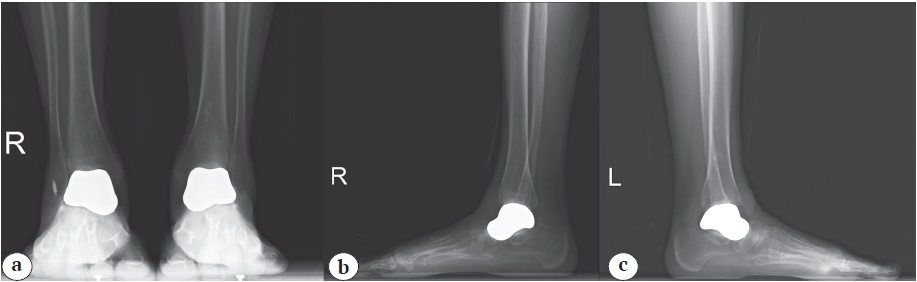

По данным компьютерной томографии выявлены очаги аваскулярного некроза, деструкция и фрагментация таранных костей обеих стоп (рис. 1).

Рис. 1. МСКТ-сканы голеностопных суставов — отмечаются очаги деструкции и коллапс таранных костей обеих стоп: a — коронарный скан голеностопных суставов; b — сагиттальный скан правой стопы; c — сагиттальный скан левой стопы

Figure 1. MSCT scans of the ankle joints demonstrating the destruction foci and collapse of both talus bones: a — a coronal scan of both ankles; b — a sagittal scan of the right foot; c — a sagittal scan of the left foot